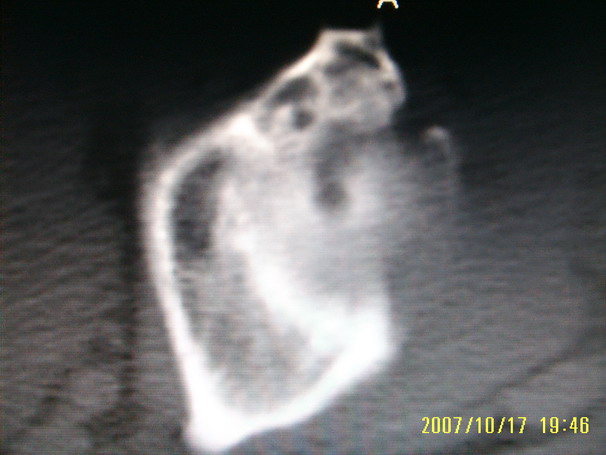

标题: CT10352:女,45岁,股骨头病变,如何诊断? [打印本页]

标题: CT10352:女,45岁,股骨头病变,如何诊断?

股骨头病变,如何诊断?

患者女,45岁,左髋部行走疼痛一年,无外伤史,无感染史。x片示囊状骨透亮区

左侧股骨头变形,密度增高,局部塌陷。多考虑:股骨头缺血性坏死伴退变!

左侧股骨头塌陷,其内囊变硬化,骨纹理改变考虑:左侧股骨头坏死及蜕变.

股骨头形态尚可,骨皮质环厚度及完整性可,病灶区以外骨质尚未见明显异常,临近髋臼骨质亦可见类似改变,考虑退变性关节面下囊变可能性大,骨样骨瘤等不排除,

股骨头形态尚可,骨皮质环厚度及完整性可,病灶区以外骨质尚未见明显异常,临近髋臼骨质亦可见类似改变,考虑1.动脉瘤样骨囊肿,2.股骨头缺血坏死,

股骨头形态尚可,骨皮质环厚度及完整性可,病灶区以外骨质尚未见明显异常,临近髋臼骨质亦可见类似改变,考虑退变性关节面下囊变可能性大

双侧股骨头形态都欠规整,外形欠光滑,尤以左侧明显,考虑双侧髋臼发育不良并退行性变